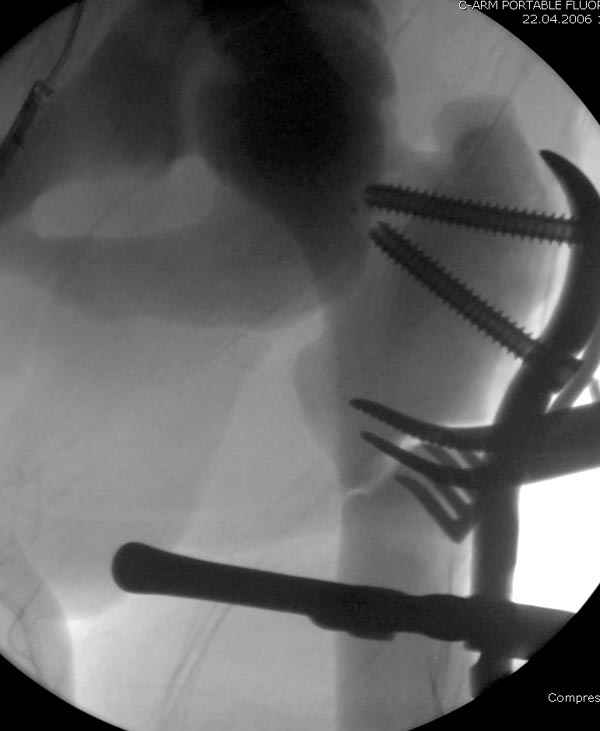

После неудачной попытки скелетного вытяжения в первом мед.учреждении, после осмотра снимков и изучения истории, поставили диагноз “Остеопетроз” или мраморная болезнь, редкая наследственная костная паталогия, где имеется нарушение формации остеокластов.

Конечно, было бы идеальным применение интрамедуллярного остеосинтеза, но учитывая прежний собственный опыт (лечил перелом бедра) и

публикации, предупреждающие о трудностях при обработке кости (иногда из-за неподготовленности инструментария результатом была неадекватная фиксация перелома, или перенос операции из-за фактора усталости оперирующего персонала), решили применить пластину (и в этом же случае был выбран Synthes plate, так что представитель за два дня

зароботал... на десерт тоже).

Заказаны были дополнительные различные дрели, и на следующий день, усиленной бригадой, больного прооперировали, потратив на каждое отверстие около 25-35 минут, хотя сверлили с охлаждением по нарастающей по диаметру сверл и с их заменой каждые 2 мм сверления.